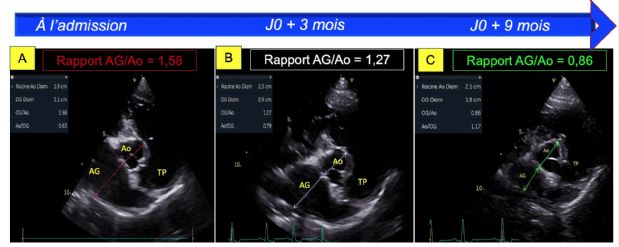

- La dilatation atriale gauche, avec un rapport atrium gauche/aorte en télédiastole augmenté égal à 1,58 (Figure 6A) ; (VU 1,2 chez le chien sain) et un volume atrial gauche télésystolique indexé au poids corporel, estimé par la méthode Simpson, augmenté et égal à 1,23 mL/kg (Figure 7A) ; (Valeur seuil 1,1 mL/kg en télésystole chez le chien sain) ;

- Une normalisation du diamètre atrial gauche en télédiastole (Figures 6C versus 6A) ainsi qu'une normalisation de son volume (Figures 7B et 7C versus 7A) ;